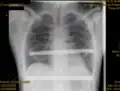

X-ray of a 15-year-old male after undergoing the Nuss procedure